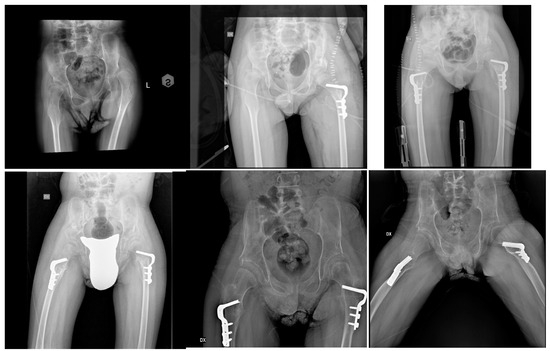

Radiographic and Clinical Results of Combined Bone and Soft-Tissue Tailored Surgeries for Hip Dislocation and Subluxation in Cerebral Palsy

2. Materials and Methods

3. Results

3.1. Acetabular Index (AI)

3.2. Reimer’s Index (RI)

3.3. Neck–Shaft Angle (NSA)